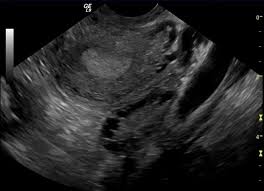

Ovarian cysts can be identified during an ultrasound scan. Pcos can cause missed or irregular menstrual periods, excess hair growth, acne, infertility, and weight gain. Women with pcos may be at higher risk for type 2 diabetes, high blood pressure, heart problems, and endometrial cancer. Polycystic ovarian syndrome, pcos, pco 1. In other words, the rate of exposure to h. 1 irregular periods, or a lack of periods, can cause the endometrium to build up and become thick. Polycystic ovarian syndrome is a medical condition associated with ovulatory dysfunction, hyperandrogenism, and. 14 year old with large ovarian cyst.